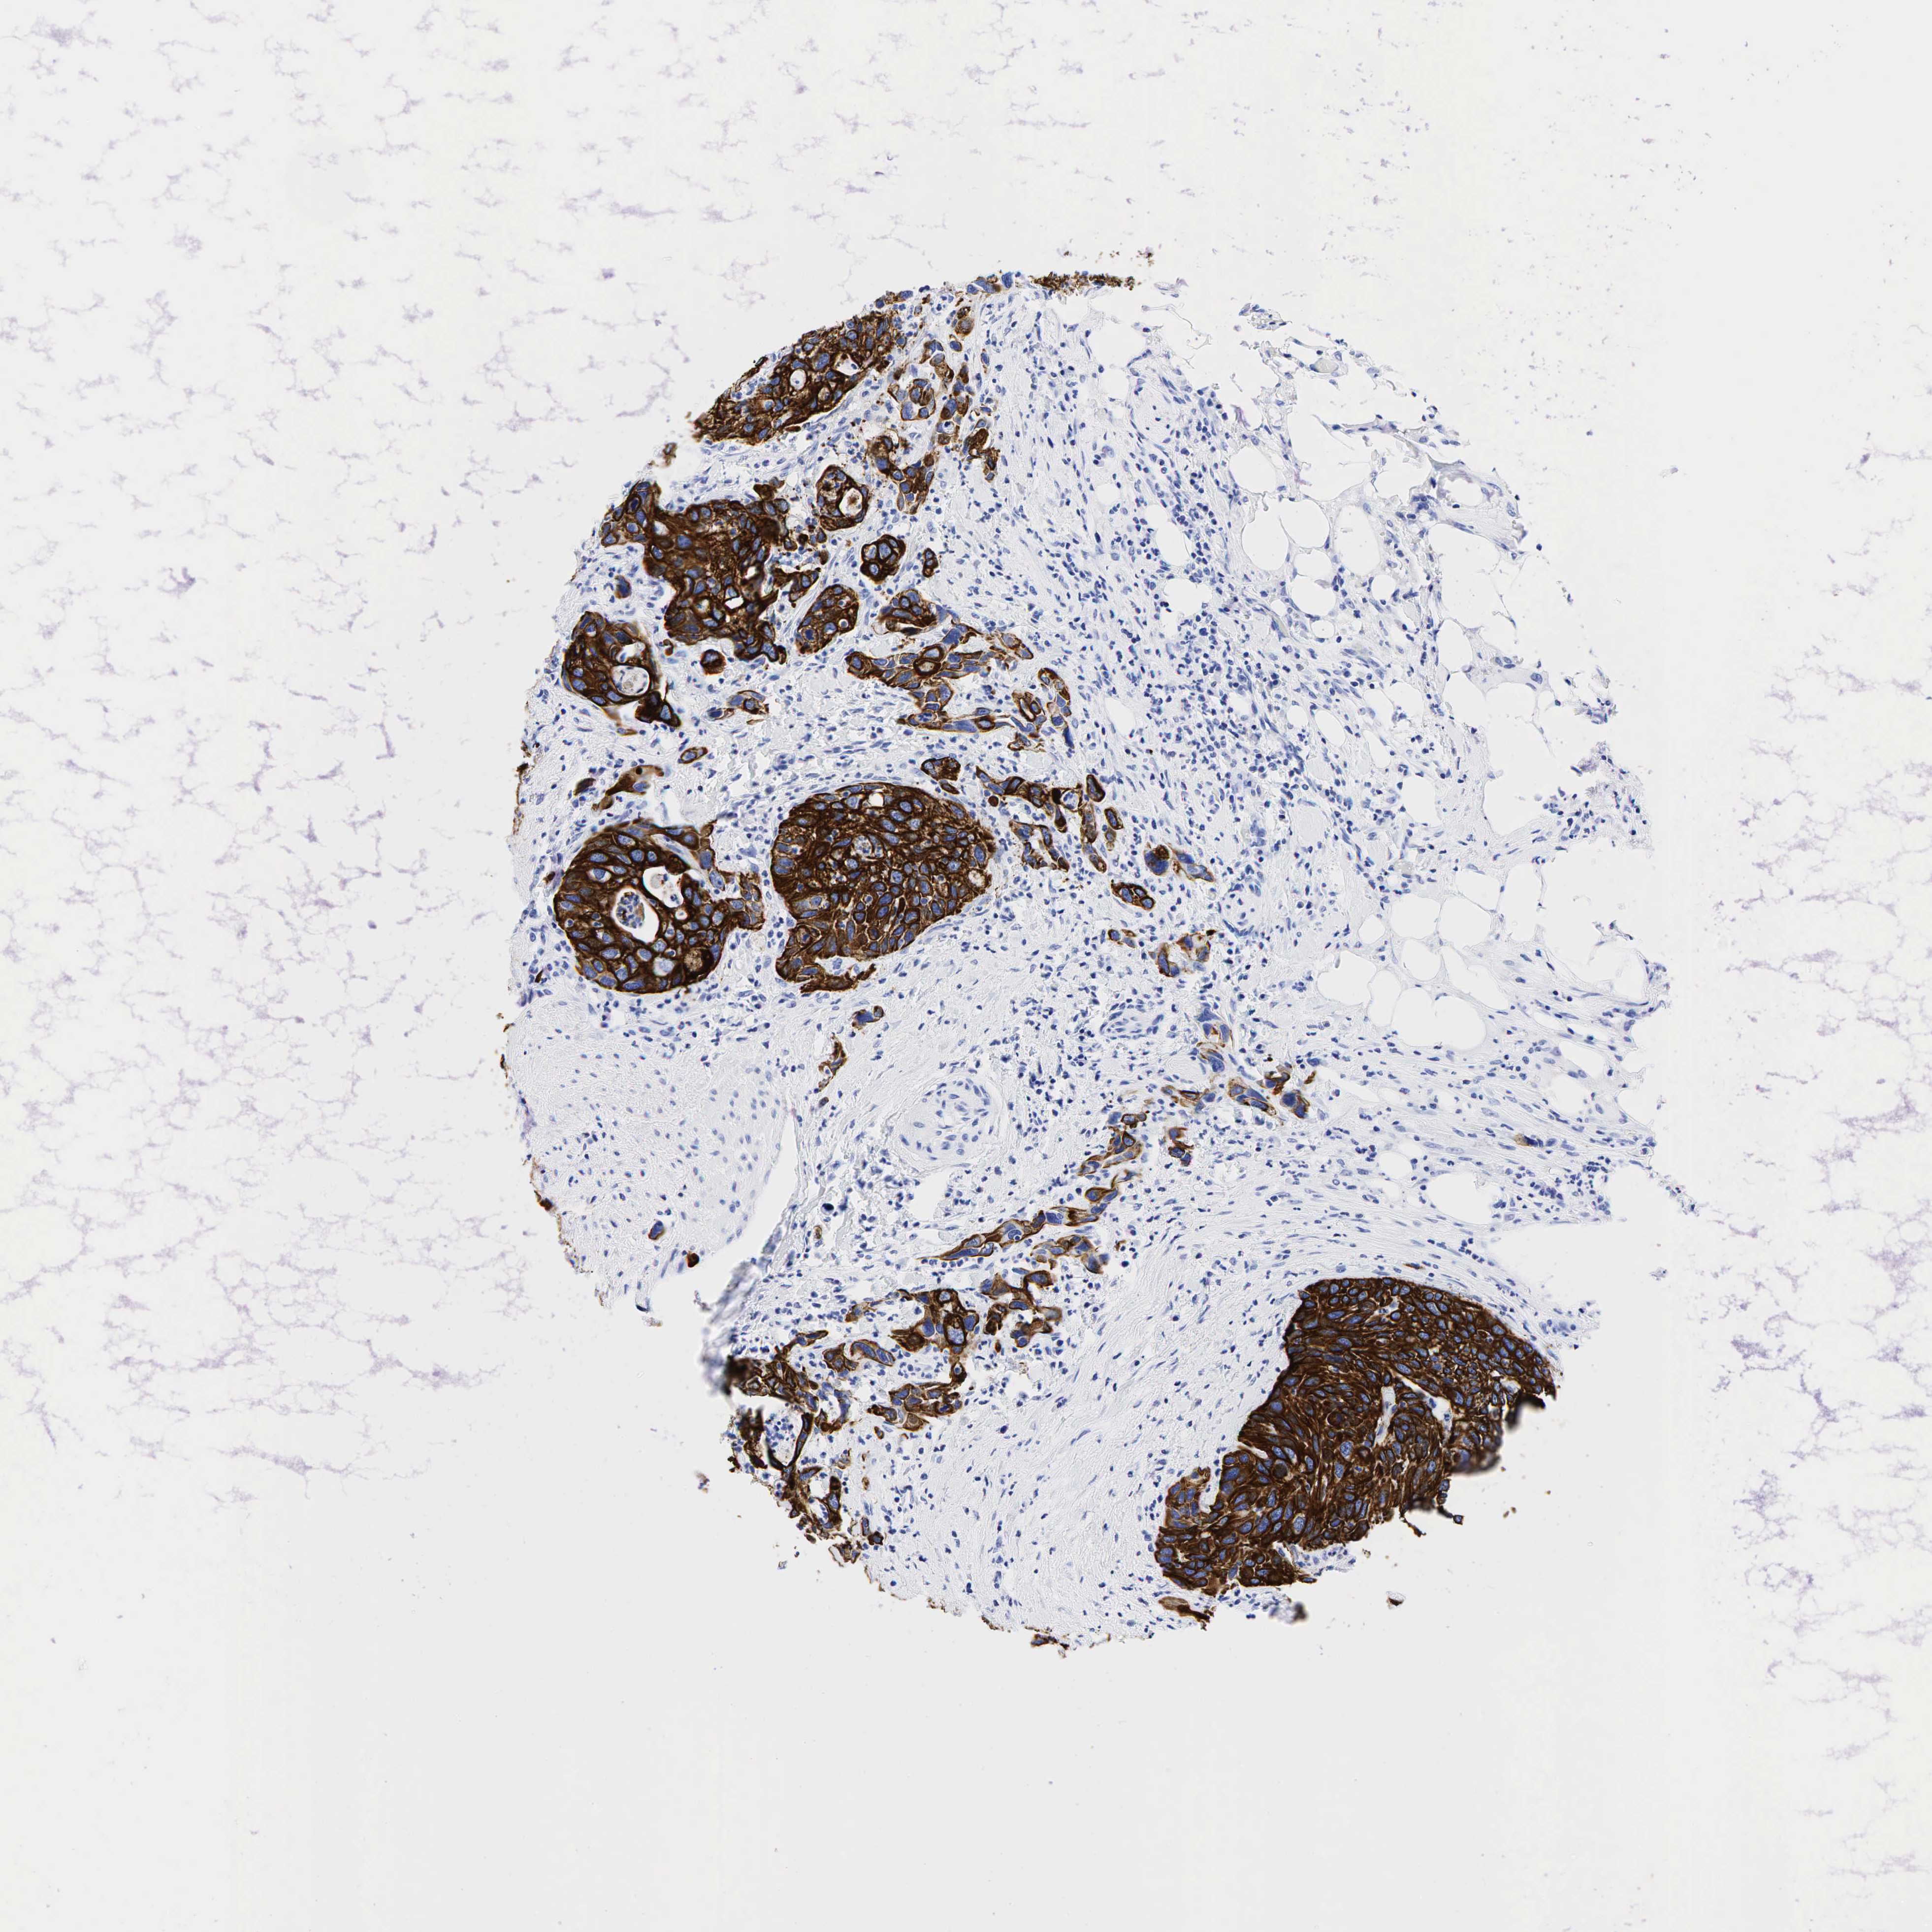

UROTHELIAL CANCER - Protein expressioni

A mouse-over function shows sample information and annotation data. Click on an image to view it in a full screen mode. Samples can be filtered based on level of antibody staining by selecting one or several of the following categories: high, medium, low and not detected. The assay and annotation is described here.

Antibody stainingi

Antibody staining in the annotated cell types in the current human tissue is reported as not detected, low, medium, or high, based on conventional immunohistochemistry profiling in selected tissues. This score is based on the combination of the staining intensity and fraction of stained cells.

Each image is clickable and will lead to virtual microscopy that enables deeper exploration of all samples and also displays staining intensity scores, fraction scores and subcellular localization as well as patient and tissue information for each sample.

Antibody HPA002465

Antibody CAB000031

Staining

High

Medium

Low

Not detected

Intensity

Strong

Moderate

Weak

Negative

Quantity

>75%

75%-25%

<25%

None

Location

Nuclear

Cytoplasmic/membranous

Cytoplasmic/membranous,nuclear

Urothelial carcinoma, Low grade